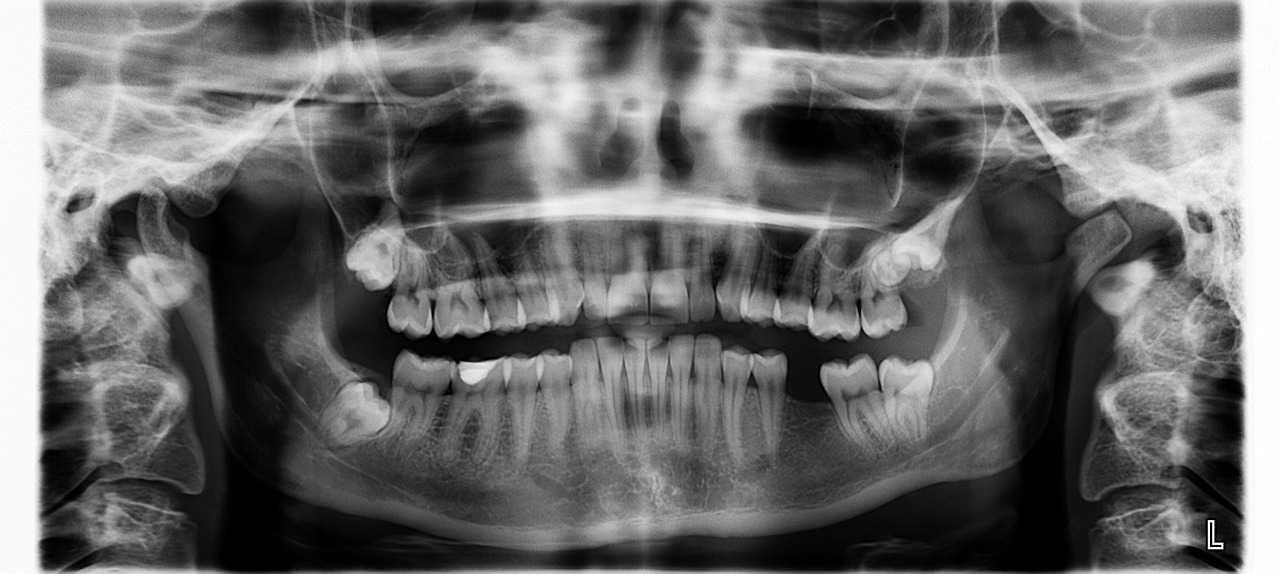

X-Ray is a diagnostic imaging procedure that helps dentists view the internal structures of your teeth, roots, and jaw to detect issues not visible during a regular examination.